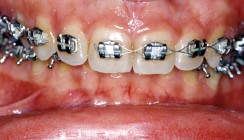

• 2) Orthodontie: Orthodontie zur Ausformung und Abstimmung der Zahnbögen aufeinander und Dekompensation der skelettalen Dysgnathie. Entscheidend bei der Vorbereitung waren die Protrusion und das Torque der Oberkieferfront. Zur orthodontischen Behandlung wurde eine Multiband-Apparatur (22er Slot-Brackets) verwendet. Eine Lücke zwischen den mittleren Schneidezähnen wurde belassen, damit später eine Verbreiterung der Zähne möglich wird, sodass eine Harmonie in der Frontregion erreicht werden kann.

• 5) Orthodontie zur Feineinstellung der Okklusion. Während der Ruhestellung der Unterkiefersegmente (7 Tage postoperativ) wurde im Bereiche der Okklusionsinterferenzen, insbesonders in der Vertikalen, Up-and-down-Gummizüge eingesetzt. Nach Entfernung der maxillomandibulären Fixation erfolgte die Feineinstellung der Okklusion. Diese Phase dauerte ca. fünf Monate.